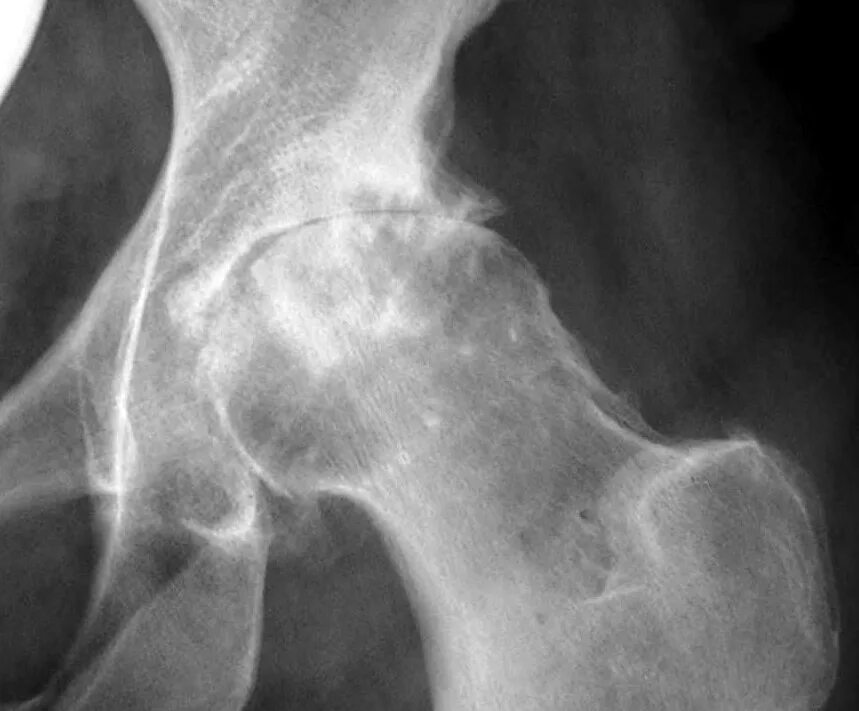

Коксартроз коленного сустава тазобедренного